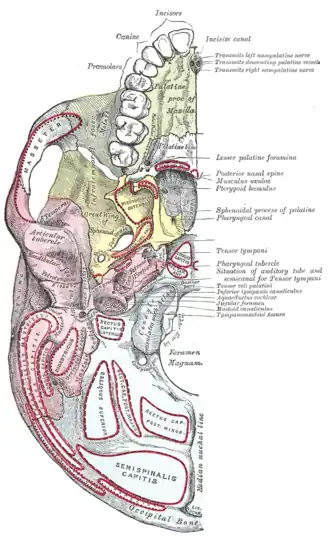

Left maxilla. Outer surface. Base of skull. Inferior surface.

Base of skull. Inferior surface. Unerupted permanent teeth underlie the deciduous teeth.